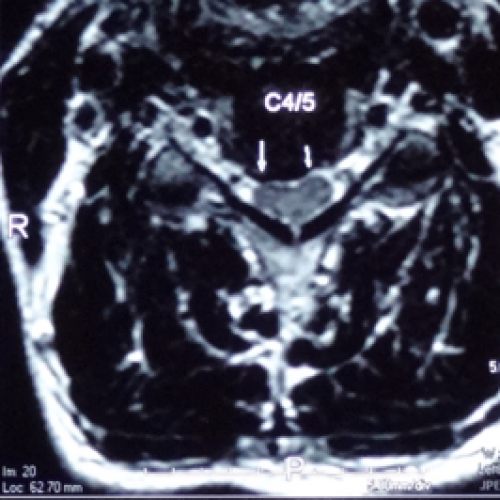

椎間盤( 軟骨) 在上下兩節脊椎骨之間,由內層的骨髓核( 啫喱狀物) 及外層的纖維環所構成。椎間盤的作用是吸收脊椎所承受的壓力,亦有避震的作用,當我們擺動身體,向前或向後彎腰時, 軟骨亦同時作出不同的形狀來配合身體的動作。但隨著年齝增長及長期身體負重,到了三十歲左右, 髓核會開始脫水和變質,吸收壓力的能力亦會降低,同時纖維環也開始出現退化。當我們不覺地做 出一些不當的姿勢或動作,便可能造成椎間盤 ( 軟骨 ) 突出。